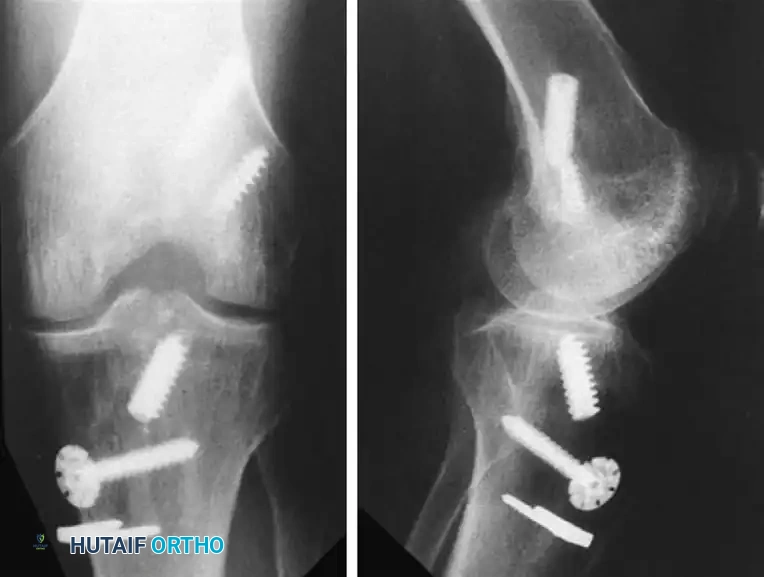

The management of retained hardware is a technically demanding aspect of revision surgery. The fundamental rule is that hardware should be removed only if absolutely necessary. Unnecessary removal of well-fixed, asymptomatic hardware that does not interfere with the new anatomic tunnels creates large cavitary bone defects that complicate subsequent fixation.

FIGURE 45-128: If possible, original fixation hardware should be left in place during revision anterior cruciate ligament reconstruction to avoid creating unnecessary osseous defects.

When hardware removal is mandatory (e.g., intersecting the new tunnel trajectory), the following principles apply: